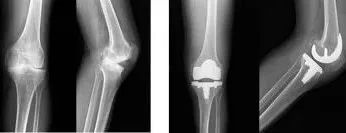

③人工关节置换术

对于关节强直、畸形及功能丧失的血友病性关节炎的患者,需要考虑人工关节置换手术,但必须在积极补充凝血因子的前提下,以确保手术安全。